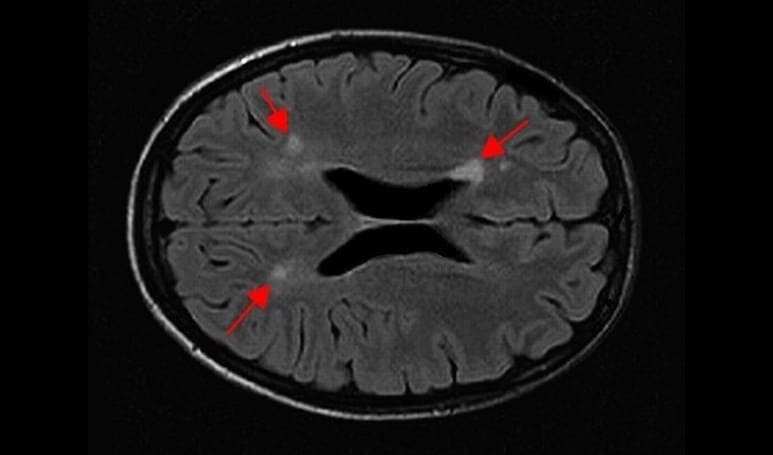

Die Multiple Sklerose (MS) ist eine chronisch entzündliche Erkrankung des Zentralnervensystems, bei der fehlgeleitete Immunzellen die Isolierung der Nervenzellen in Gehirn und Rückenmark angreifen. Die oft zahlreichen (multiplen) herdförmigen Entzündungsareale führen je nach ihrem anatomischen Ort zum Ausfall unterschiedlicher Funktionen und folglich zu höchst verschiedenen Beschwerden – z.B. Verschwommen-Sehen, Doppelbilder, Kribbeln oder Taubheit an Armen/Beinen, oder Lähmungen.